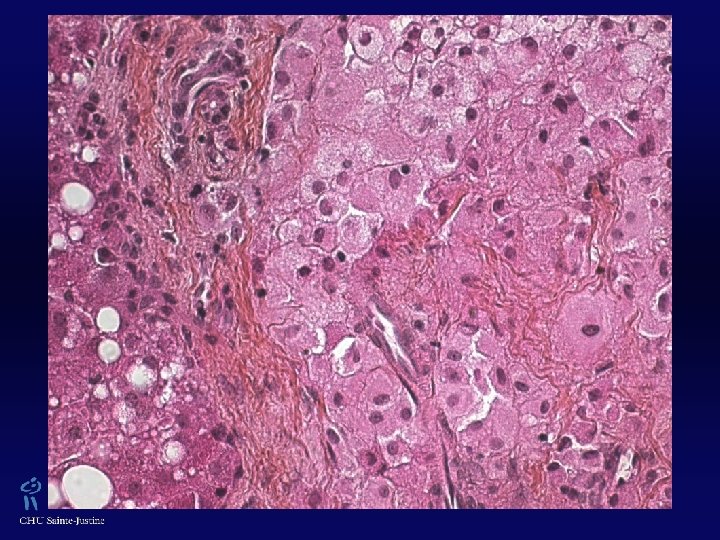

XGJ w Trois types cellulaires : w Cellules mononucléées w Cellules géantes mutinucléées, ± de type cellules de Touton (› lésions cutanées, absentes dans les formes jeunes) w Cellules fusiformes w ± Vacuoles cytoplasmiques, avec aspect xanthomateux w Éosinophiles 0/+++ w Vimentine +, CD 68 +, Facteur XIIa +, Fascine + w Protéine S 100 ± w CD 1 A -, absence de granules de Birbeck (ME)

Histiocyte Lysosomes contenant des inclusions denses

Hépatocyte Mitochondries normales Gouttelettes lipidiques Inclusions dans RE d’α-1 -antitrypsine

Faits saillants… w Difficulté diagnostique… w Deux biopsies hépatiques nécessaires w Absence d’autre localisation w Association avec NF-1 décrite ! w Deux taches "café-au-lait" w Mutation gène de Neurofibromine (17 q 11. 2) ? w Accumulation d’α-1 -antitrypsine w Dosage sérique normal w Hétérozygote Pi. SZ ? w Accumulation secondaire aspécifique ?